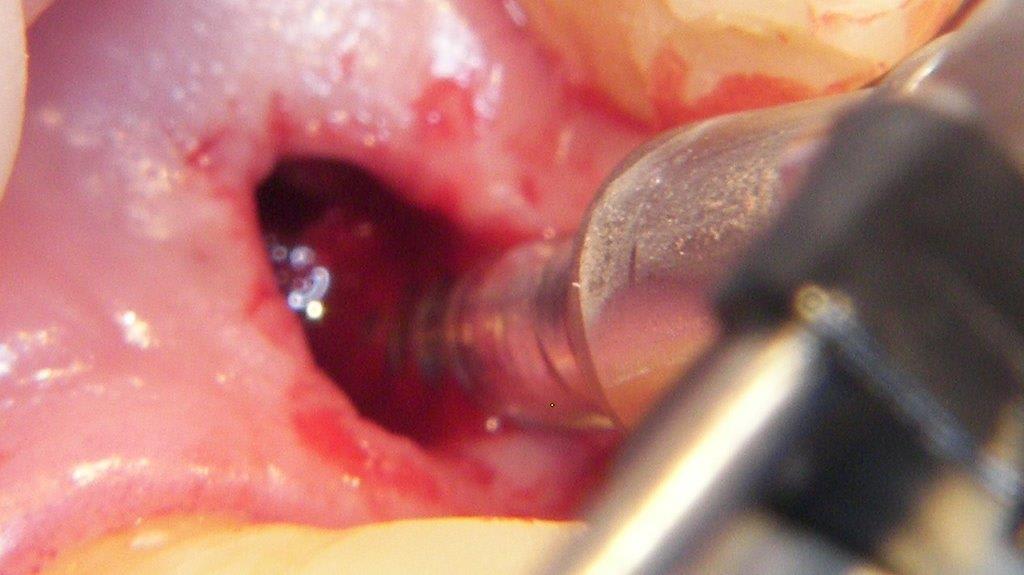

pour ceux que ça intéressent, une petite utilisation d'expansion de la paroi palatine, sur une avulsion d’incisive(racine fendue). toutes mes excuses pour la mauvaise qualité des photos.